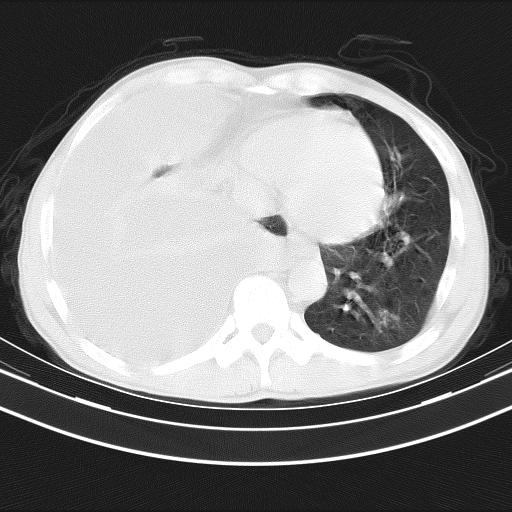

男性,44岁,结核病史多年。现胸闷气短,咳嗽,偶咳血。

右侧胸腔积液

右肺下叶不张

双肺多发结节影最分空洞形成考虑占位不除外结核

双肺陈旧性病变

1、右侧大量胸腔积液伴右肺压缩性膨胀不全,建议抽液治疗后复查 2、两肺继发性tb伴空洞形成。

1)两肺继发性肺结核伴空洞形成,左肺多发性结核球。2)右侧大量胸腔积液伴右肺部分膨胀不全。3)纵隔淋巴结肿大。